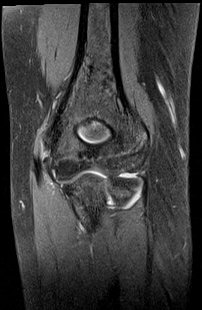

ÆÈ²ÞÄ¡ ̫̿ ÃøºÎÀÎ´ë ÆÄ¿­ ¹× °ß¿­°ñÀý(±×¸² 8, 9)